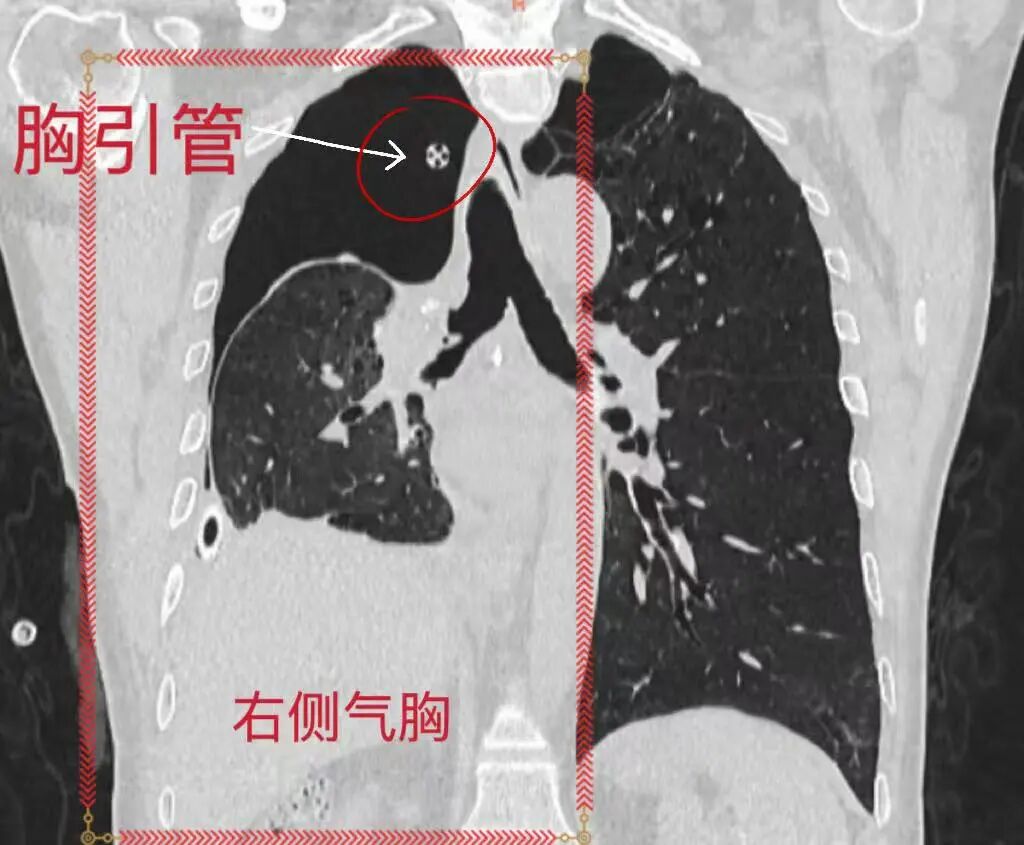

BPF封堵前右侧气胸持续引流

精准定位后,团队通过内镜分次注入混合生物制剂实施封堵,成功治愈多处瘘口。术后患者胸腔闭式引流瓶无气体溢出,2根胸腔引流管先后顺利拔除,恢复情况良好,复查胸部CT后康复出院,整个诊疗过程微创、安全、顺畅。